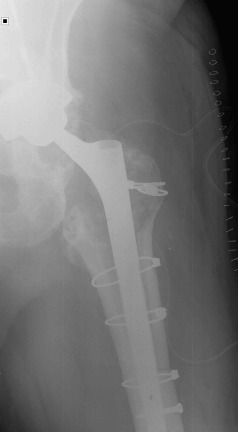

In October 2013 (two years and one month after the revision procedure), the patient was surprised by a storm and was struck by lightning while strolling. He remained conscious and suddenly he was unable to bear weight on the left leg and a deformity on his left lower extremity was detected. His neurovascular status was stable. Plain radiographs demonstrated a displaced fracture through the base of the neck of the femoral component (Fig. 3 ). The patient underwent revision THA through a posterior iterative approach. A transfemoral osteotomy was required to extract the stem, which presented no signs of loosening. Prophylactic Dall-Miles wiring was done to prevent fractures just under the osteotomy. The selected component for the revision was a modular curve Revitan® (Zimmer, Winterthur, Switzerland) system. It was a 200 × 180 mm stem with a distal locking screw of 36 mm and a metaphysis of 75 mm with 15° of anteversion. The head was a #36 metallic. Finally, the osteotomy was fixed with four Dall-Miles cerclages (Fig. 4 ). After the surgery, the patient needed two blood transfusions due to postoperative anaemia. The postoperative course was otherwise unremarkable and the patient was allowed partial two-crutch assisted weight-bearing. The patient was discharged with an active range of motion of 75° of hip flexion and 15° of hip abduction. Three months after surgery, the radiographs demonstrated consolidation of the osteotomy. After one year, the patient is satisfied, without pain and had returned to work.

Fig. 3. Anteroposterior radiograph after the lightning strike. The fracture locates through the base of the neck. |